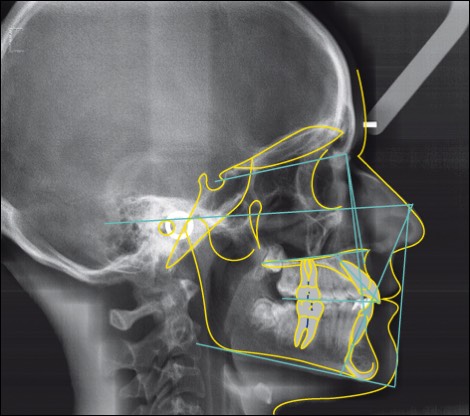

Image 2D du profil du visage, des mâchoires et des dents. Utilisée principalement en orthodontie pour évaluer la croissance et planifier le traitement.